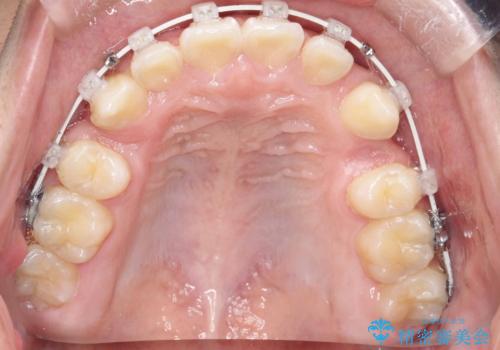

- ワイヤー(審美装置)

矯正の精密検査の結果上顎左右4番の計2本を抜歯し、審美性に配慮したワイヤー矯正装置(審美装置)を用いて治療を行いました。

八重歯などの歯列のデコボコが綺麗に改善され、患者様にも大変喜んでいただけました。また、咬み合わせが深い「ディープバイト」も併せて改善し、見た目だけでなく機能面でもバランスの取れた咬合を獲得しています。